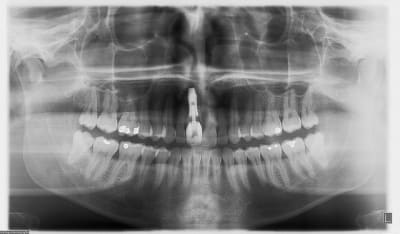

pluton

18/10/2011 à 12h22

joli D57...;-)

çà manque un peu de cas en ce moment...alors en voilà un ptit au passage...

11 avec résorption interne

EII avec MCI sur du dentium (4.5/14) comblement du gap vestibulaire avec du kasios tcp (très constant dans les résultats...et très économique)

pas de photos de chir par contre...j'ai du les effacer par erreur...grrrr...

la prothèse d'usage a été réalisée par ma petite associée...mais j'étais là pour superviser et faire quelques photos...;-)